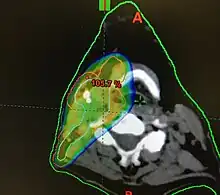

Diagram of radiation therapy contours used in treating a right tonsillar cancer

Transverse radiation contours used in treating cancer seen on above CT scan and in machine set up below

Concerns over the morbidity associated with traditional open surgical en-bloc resection, led to exploring alternative approaches using radiation.[121] Intensity modulated radiation therapy (IMRT) can provide good control of primary tumours while preserving excellent control rates, with reduced toxicity to salivary and pharyngeal structures relative to earlier technology. HPV+OPC has shown increased sensitivity to radiation with more rapid regression, compared to HPV-OPC.[132] Generally, radiation can safely be delivered to the involved side alone (ipsilateral), due to the low rate of recurrent cancer on the opposite side (contralateral), and significantly less toxicity compared to bilateral treatment.[lower-alpha 5][134][133] IMRT has a two-year disease free survival between 82 and 90%, and a two-year disease specific survival up to 97% for stage I and II.[135][136]